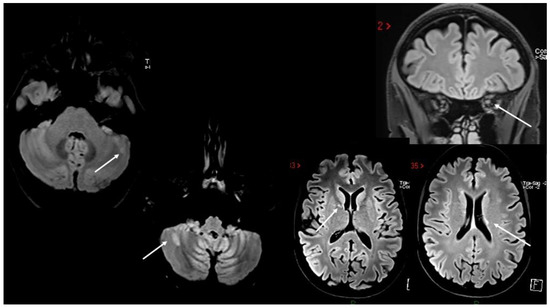

5. MS Relapses after Vaccine Exposure

| Rinaldi et al. [68] | BNT/1st | 2 weeks | Cerebellum/BS | ST | + | + | IFNb | NA |

| $ Al-Midfai et al. [71] | JJ/2nd | 2 weeks | Uncertain (unilateral motor deficit) | - | + | NA | - | NA |

| $ Maniscalco et al. [72] | BNT/1st | 2 days | Unilateral SM deficit | ST | + | NA | FTY | NA |

| Kataria et al. [73] | BNT/2nd | 3 weeks | ON + SC | ST | + | - | IFNß | NA |

| Seyed Ahadi et al. [74] | Sinopharm/1st | 2 days | Paraparesis and ataxia | BS | + | NA | - | NA |

| Kayat-Khoei et al. [64] 4 cases | mRNA vaccines 1st (1) and 2nd (3) | 1–3 weeks | ON (2) BS+SC (1) Possibly SC (1) | Brain (3) | + (new SC in 2 cases) | NA | NTZ (1) FTY (1) None (2) | NA |

| $ Nistri et al. [67] 14 cases | ChadOx/1st (2) mRNA/1st (7), 2nd (5) | 2 days–3 weeks | BS/cerebellum (4) SC (6) Possibly SC (6) | Brain (13) | + | + | + (9) - (5) | NA |

| D’apolito et al. [75] | BNT/2nd | 4 days | BS/cerebellum | + | - | + | FTY | NA |